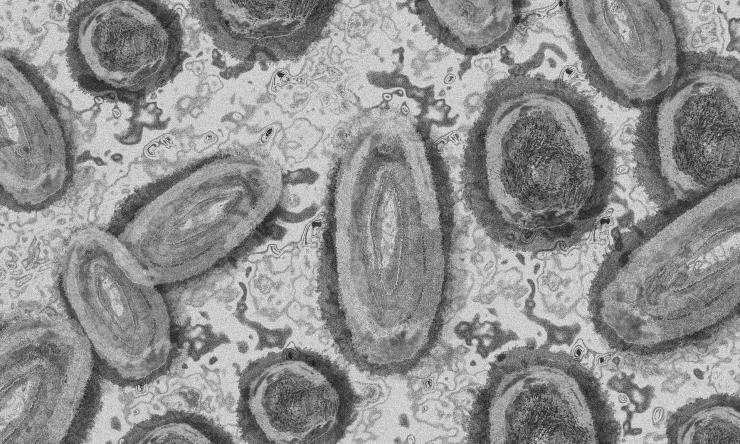

JYNNEOS contains an attenuated orthopoxvirus called modified vaccinia Ankara, which does not replicate in human cells. It is approved for administration by two subcutaneous (in the tissue beneath the skin) injections 28 days apart; however, the FDA recently authorized intradermal (between layers of the skin) administration of the vaccine for adults. This alternative intradermal dosing regimen uses one-fifth of the standard dose used for subcutaneous administration, allowing healthcare providers to administer up to five times the number of vaccine doses per vial of JYNNEOS vaccine. NIH-supported researchers demonstrated in a 2015 publication that intradermal administration at one-fifth of the standard dose induced an immune response in recipients that was comparable to the subcutaneous method of administration.